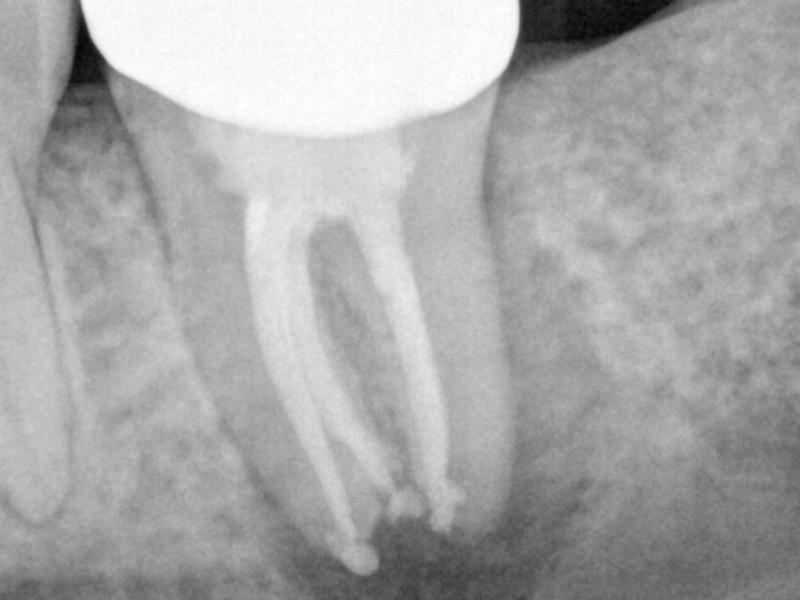

Pre-Op